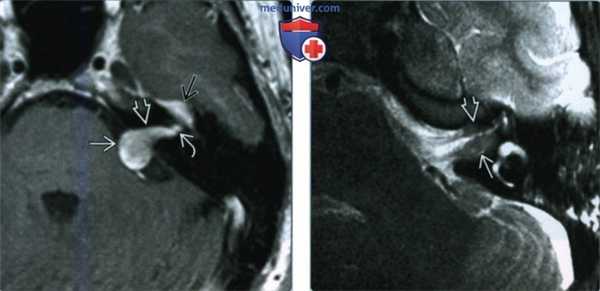

(Слева) При аксиальной КТ в костном окне у пациента с правосторонним параличом лицевого нерва визуализируется маленькая ВМЛН в ямке коленчатого ганглия. Обратите внимание на точечные костные очаги в структуре, которые позволяют отличить ВМЛН от шванномы лицевого нерва, которая также возникает преимущественно в ямке коленчатого ганглия.

(Справа) При аксиальной МРТ Т1 С+ FS у этого же пациента определяется ВМЛН, накапливающая контраст, в области коленчатого ганглия. Область точечных кальцинатов выглядит как гипоинтенсивный фокус.